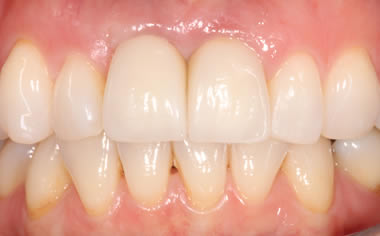

More front teeth replaced by dental implants

Case Three (4 images)